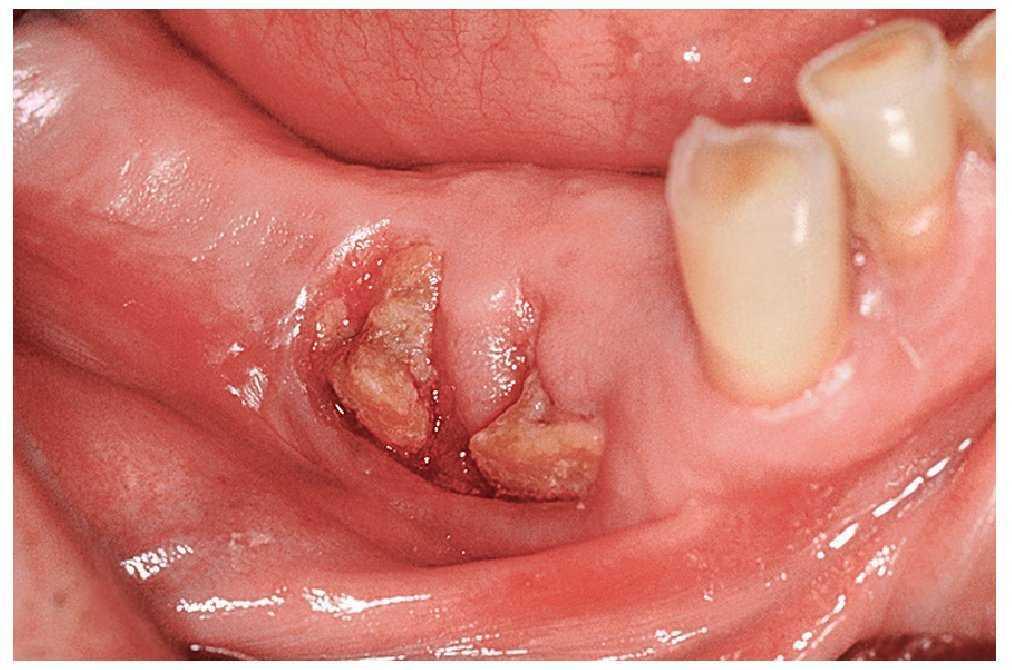

A esto se pueden añadir diferentes grados de movilidad dentaria, trastornos de la sensibilidad sobre todo en el área del mentón y del labio inferior, y también fístulas. En casos de afectación extensa pueden aparecer trayectos fistulosos extraorales (figs. 4a a 4c).

Figura 4a. Osteonecrosis muy marcada con áreas extensas de hueso expuesto, fístulas múltiples y tumefacciones mucosas.

Figura 4b. Misma paciente: imagen del mentón desde la parte inferior con fístulas extraorales.